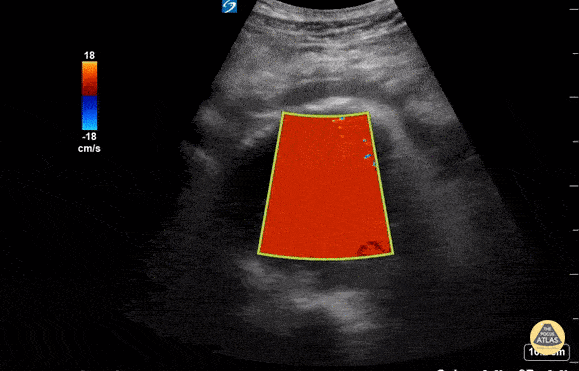

A 76 year old male presented to the ED for abdominal pain and syncope. He was tachycardic but normotensive. US performed with Sonosite 5-2MHz C60 probe with patient in supine position and probe held in transverse orientation revealed a AAA measuring ~9cm in AP diameter at its largest point. The AAA had an anechoic center with echogenic material in the posterior lumen, representing cholesterol deposit. Free fluid was seen anterior to the AAA suggestive of rupture which was confirmed by STAT CTA Aortagram. Patient was admitted to the OR for surgery. In this scenario, POCUS was a safe, non-invasive study that played a critical role in diagnosis of a ruptured AAA and accelerated surgical intervention. Susan Dhamala, MS4, Drexel University College of Medicine Brenton Elliot, MD, Crozer Chester Medical Center Matthew Cully, DO, Nemours/Alfred I. duPont Hospital for Children Kevin Conor Welch, DO, Crozer Chester Medical Center Max Cooper, MD, RDMS, Director of Emergency Ultrasonography at Crozer Chester Medical Center